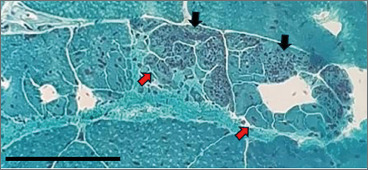

Case presentation: A 34-year-old male with congenital clubfoot, post-exertional rhabdomyolysis, and a family history of sudden cardiac death in mid-life was evaluated for a severe rhabdomyolysis requiring multiple hemodialyses. Clinical evaluation showed mild distal myopathy signs, with CK levels around 3000 IU/L and muscle biopsy revealing desmin- and dystrophin-positive cytosolic protein aggregates/fibre splitting. After a minor SARS-CoV-2 infection at 55, modest signs of cardiomyopathy were observed via cardiac MRI, without patterns indicative of myocarditis. Subsequently, NGS analysis identified a variant in the LDB3 gene, potentially correlated with the clinical-histological-radiological picture, thus broadening the phenotypic spectrum of LDB3-related distal myopathies. Additionally, a possible link was suggested between the viral infection and the exacerbation of the otherwise subtle cardiomyopathy. In the context of hyperCKemia and positive family history for unexplained cardiac abnormalities, broad-spectrum NGS testing, and cardiac MRI in selected cases, should be considered for timely diagnosis and interventions.